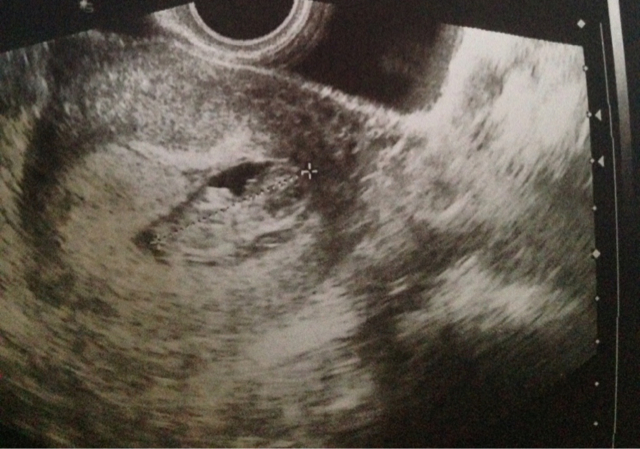

due cuoricini per i due fagiolini.